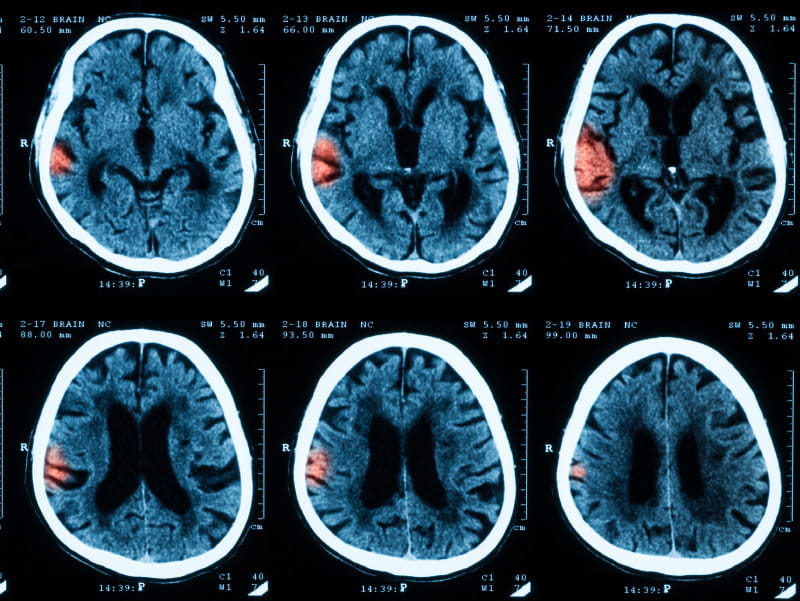

Exposure to ozone may be associated with intracerebral hemorrhage, a type of bleeding stroke, according to new research.